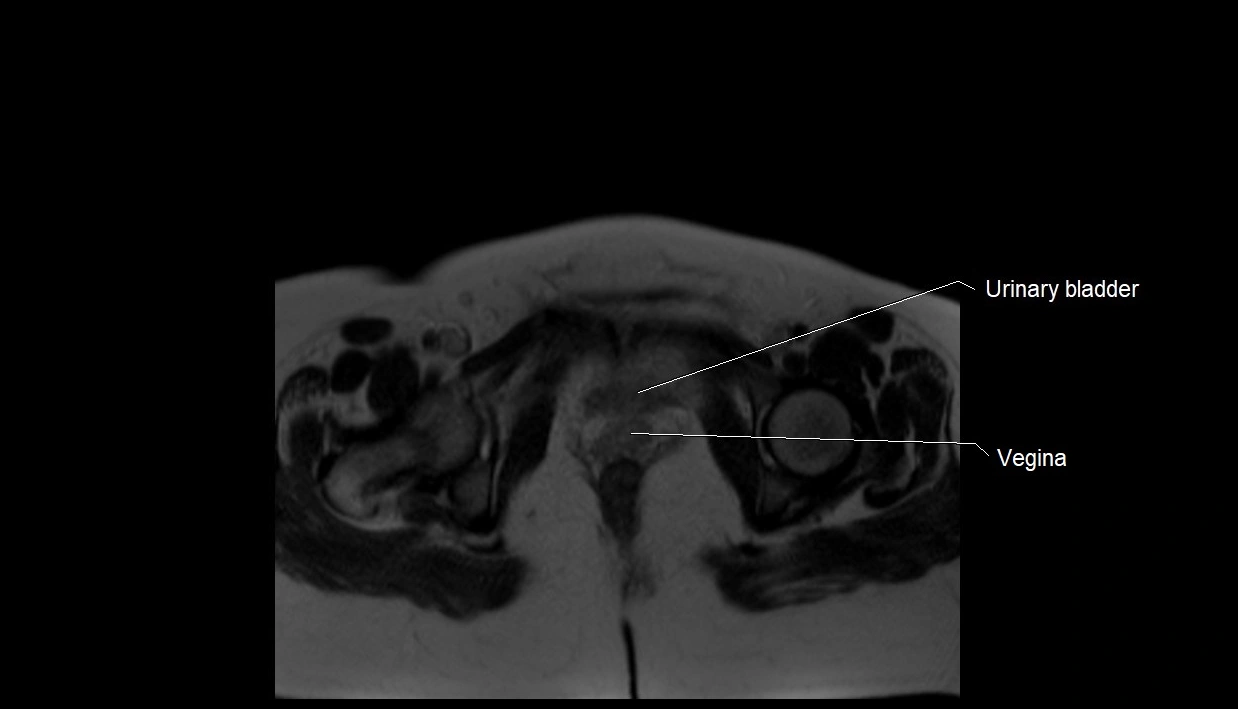

Relations

• Enclosed within the amniotic sac, bounded by the amnion and chorion

• Surrounds and cushions the developing fetus

• In continuity with maternal circulation through placental and transmembrane exchanges